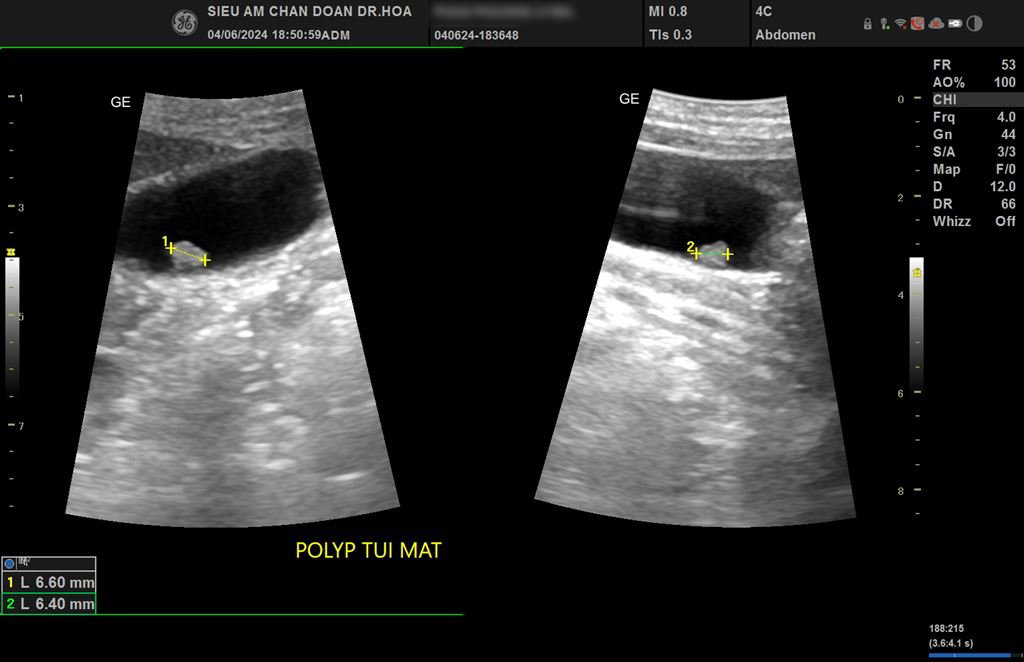

Một cô khách trẻ đã từng khám tổng quát ở một phòng khám Quốc tế chẩn đoán Sỏi túi mật và hôm nay đến Phòng siêu âm chẩn đoán Dr Hoa để kiểm tra Sỏi túi mật như thế nào? Khi đặt đầu dò mình thấy là Polyp túi mật nhưng chẩn đoán này sẽ khác hoàn toàn với Sỏi túi mật như cô được biết trước đó, mình phải làm sao cho cô ấy tin đây là Polyp chứ không phải Sỏi như cô đã từng khám mà Bs tư vấn cho cô trước đó? Polyp túi mật là một cấu trúc echo dày, không có bóng lưng (thậm chí phổ Doppler màu không xảo ảnh lấp lánh (Twinkle artifact)), không thay đổi theo tư thế. Mình siêu âm thích chụp hình rõ, chuẩn và đẹp!